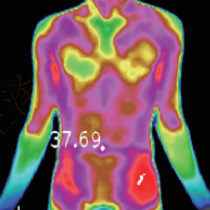

Assistance in syndrome differentiation in TCM

It can form the temperature distribution image of the human body by obtaining the infrared radiation signals of different strengths of body parts. It can assist in syndrome differentiation in TCM, physical assessment in TCM, meridian point exploration and treatment effect evaluation. In terms of treatment effect evaluation, it is possible to specify the location, onset time, duration and effect degree of drugs, acupuncture or other treatment methods, objectively and accurately evaluating treatment methods.